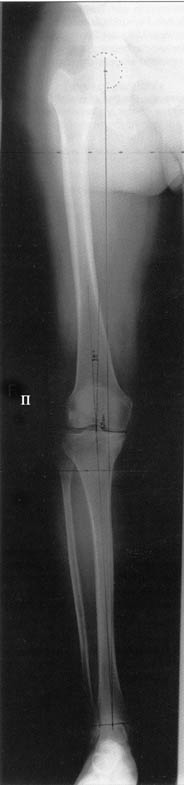

Хотя любого больного она не в меньшей степени интересовала. При всех видах остеотомий обязательным требованием являлась восстановление баланса пассивных и динамических сил путем восстановления оси конечности, стабильности связочного аппарата и контроля над мышечной активностью при осевой нагрузке. Как правило, учитывалась сохранность гиалинового хряща на компенсирующем нагрузку мыщелке бедра или большеберцовой кости. Предоперационное планирование осуществляли с поднагрузочных рентгенограмм обоих конечностей.

Поделитесь, пожалуйста, опытом, как Вам удается выполнять такие качественные рентгеновские снимки всей ноги полностью? На трех кассетах одновременно? Стыки кассет обычно <крадут> 1-2 см изображения. На снимке Вашего пациента <украденных> участков нет!

Качественные под нагрузочные рентгеновские снимки, получаются благодаря современному рентгеновскому оборудованию фирмы SIEMENS, (подробности могу уточнить у рентгенологов), а качественно стыковать (прозрачный скотч) научились с годами, но это для публикаций, для работы достаточно скрепить степлером по анатомическим осям с учетом толщины диафизов и грамотно расчертить. Пособие с удовольствием отправлю.